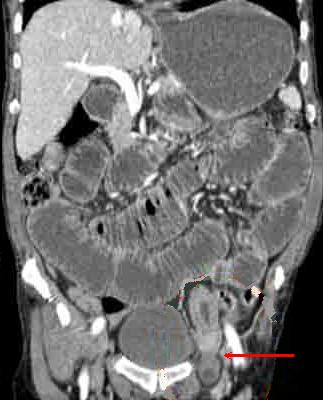

- Occlusion des hernies inguinales etranglees :

Aspect radiologique de occlusion des hernies etranglee est

image de l'obtacle se situe a la region inguino-scrotale (

hernie crurale ou hernie au dessus de arcade crurale ) , au

trous obturateurs ou a la ligne blanche + Image de

distention de l'intestin en amont de l'obtacle

| Hernie inguinale etranglee : Image TDM en

coupe axiale a travers L5 |

|

Hernie

inguinale etranglee : Meme cas en coupe axiale a

travers symphyse pulbienne |

| Hernie inguinale etrangle : Image

d'engage du grele dans fossette inguinale

moyenne + image de distension de l'intestin au

dessus de l'obstacle ( fleche rouge ) . |

La TDM est tres

l'interet de presiser facilement le type de hernie :

hernie inguinale direct etrangle avec image de grele

en de dans des vaisseaux epigastriques .La TDM peut

differentiele avec les autres masses de la region

scrotale . |